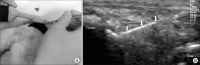

Method: New Zealand white rabbits (N=21) were randomly divided into three groups. Three different doses (0.25 mg, group 1; 0.5 mg, group 2; and 1.0 mg, group 3) of collagenase were injected twice into both knees of each group under an ultrasound guidance. The mean platelet concentration of the PRP fraction was 2,664±970×10(3)/µl and was enriched 8.2-times, compared with the whole blood. PRP (0.3 ml) was injected into the left knee and saline (0.3 ml) into the right knee at 4 weeks, and macroscopic and histological scores of both injected knees were evaluated at 9 weeks after the first collagenase injection.